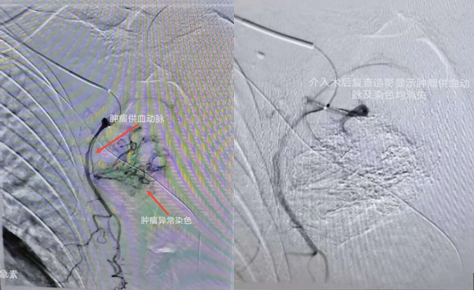

介入術(shù)中圖片

近日,吉林國(guó)文醫(yī)院淋巴瘤科與介入一科相互合作,成功為一例皮膚惡性黑色素瘤患者,實(shí)施了實(shí)體腫瘤動(dòng)脈灌注化療栓塞術(shù),患者李某某10個(gè)月前曾確診為皮膚惡性黑色素瘤,腫瘤分布在左側(cè)腋下,患者既往曾多次行靜脈化療及免疫治療,但腫瘤病情仍然繼續(xù)進(jìn)展,患者目前左側(cè)腋下腫瘤病灶增長(zhǎng)較快,伴有局部脹痛感,淋巴瘤科左淑波主任綜合分析患者病情后,邀請(qǐng)介入一科韓長(zhǎng)清主任進(jìn)行共同商討治療方案,評(píng)估是否可行介入手術(shù)治療,經(jīng)兩位主任共同商討后決定,可給予患者行腫瘤供血?jiǎng)用}化療栓塞術(shù)介入治療。介入術(shù)中非常順利,成功尋找到腫瘤供血?jiǎng)用}并給予治療,術(shù)后患者恢復(fù)良好,疼痛癥狀有所改善。